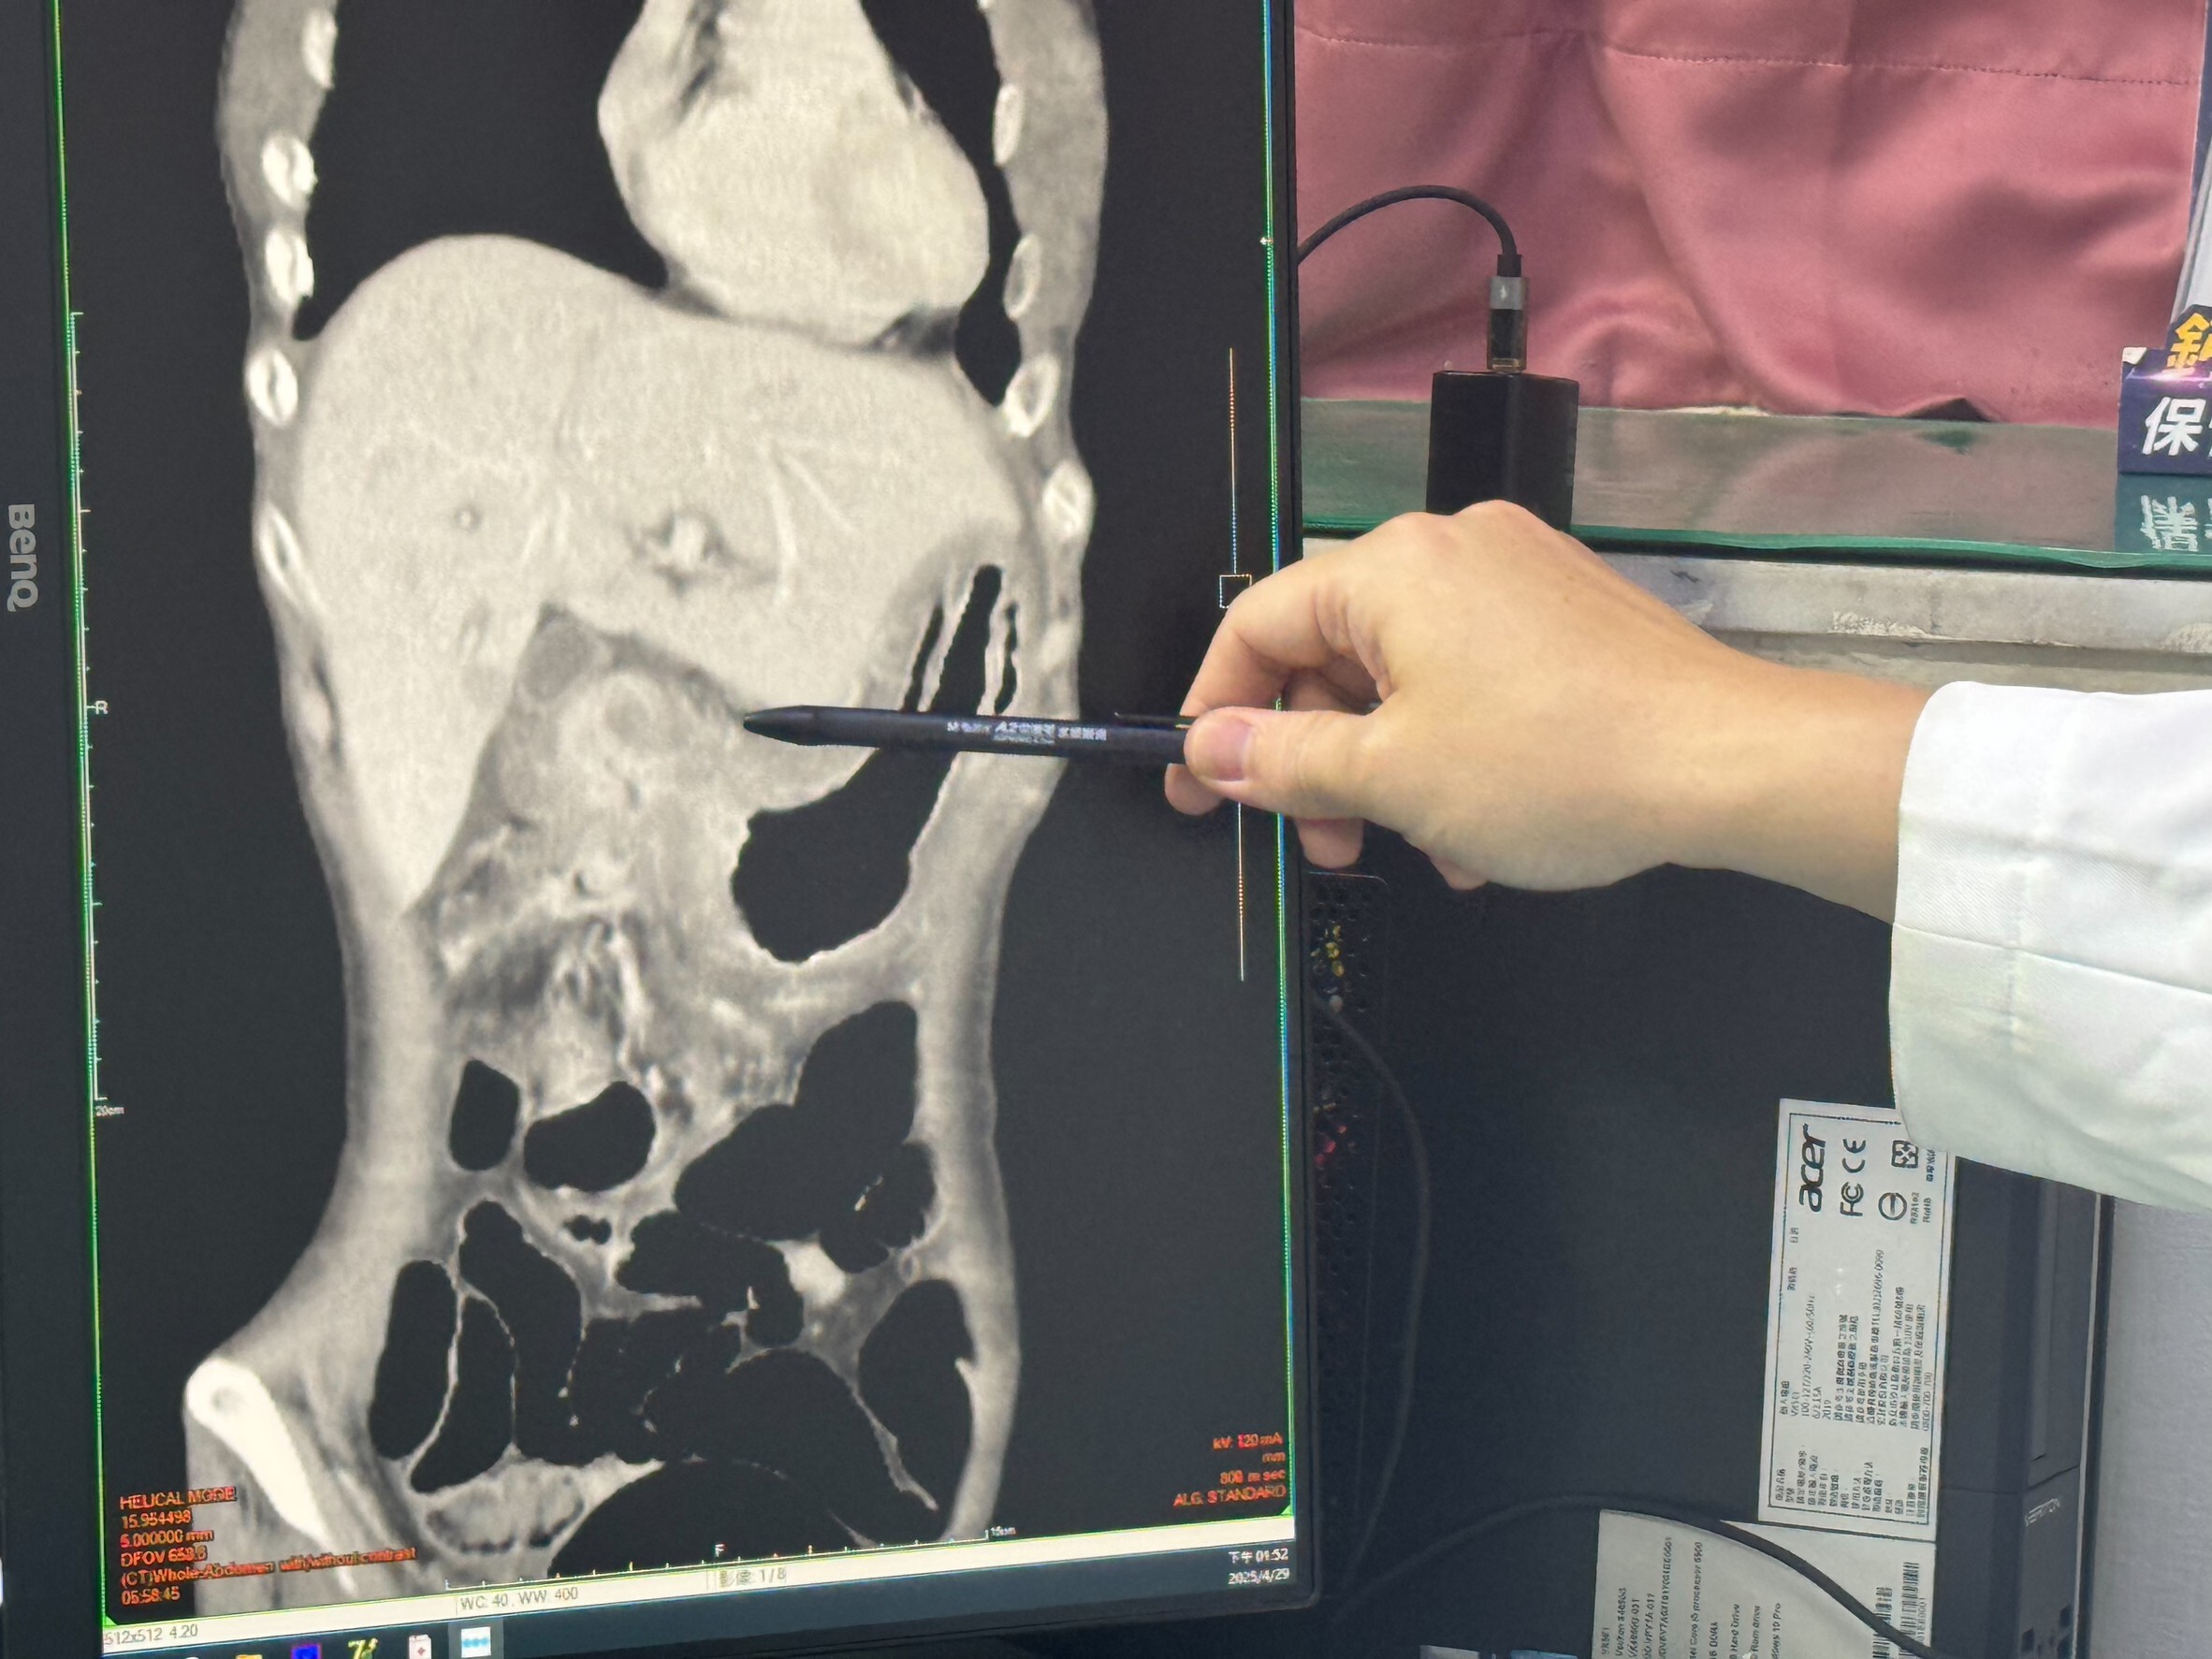

▲ 外科主任邱昱瑞說,一名40多歲患者因胃潰瘍造成腸阻塞。(圖/李綜合醫院)

經過詳細檢查,醫師發現患者的胃潰瘍已經嚴重到影響十二指腸,導致腸阻塞。邱昱瑞指出,患者接受了胃繞道手術,將胃與小腸接通,並配合藥物治療,才逐漸恢復健康。術後一個月回診時,患者的體重已增加五公斤,氣色也明顯好轉。

▲ 一名40多歲患者因胃潰瘍造成腸阻塞。(圖/李綜合醫院)